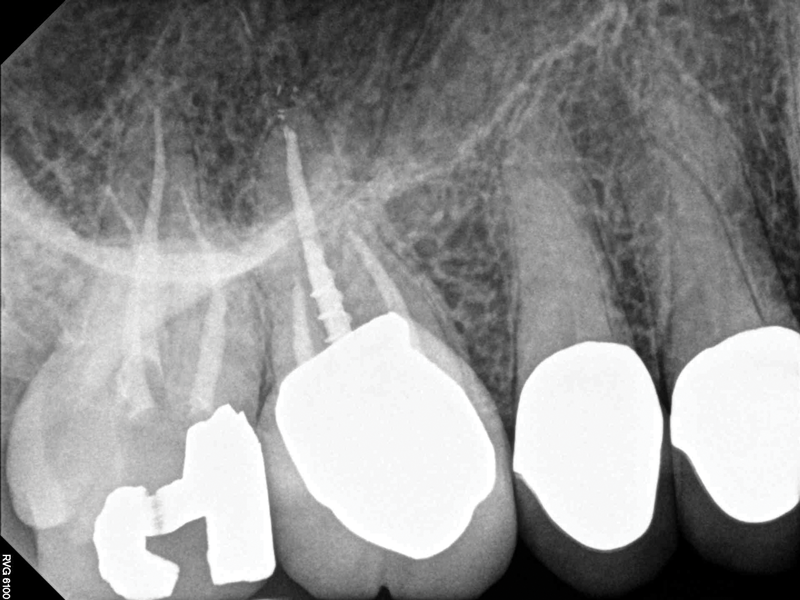

Although the patient's chief complaint was consistent with a degenerative pulpitis, the clinical and radiographic examination was initially unremarkable. All teeth in the maxillary and mandibular right quadrants were normally responsive to pulp sensitivity testing, and they were neither percussion nor palpation sensitive. Neither swelling nor sinus tracts were present, and the periodontal examination revealed normal probing depths and lack of mobility throughout the quadrant. Initial periapical radiographs revealed normal PDL spaces surrounding teeth Nos. 30 and 31, as well as a horizontally impacted No. 32 with a radiolucency within the crown in close proximity to the distal root surface of No. 31 (Figure 2 and Figure 3). Because the reported pain was severe, and in an effort to not only diagnose the issue but also offer some respite from the severe pain the patient was experiencing, an inferior alveolar nerve block was administered using 3.4 cc 0.5% bupivacaine with 1:200,000 epinephrine. Within 5 minutes of administration, the patient reported complete resolution of his pain.

Given the confirmation of a likely odontogenic source of pathology since pain was relieved by the block anesthesia, secondary periapical imaging was taken, which showed intracoronal resorption in the unerupted tooth No. 32 (Figure 4). Because of the visualizable pathology and signs and symptoms consistent with a symptomatic irreversible pulpitis, the patient was referred to an oral and maxillofacial surgeon for extraction of tooth No. 32. The patient reported complete resolution of symptoms following extraction of the affected tooth. Communication from the oral surgeon confirmed the diagnosis of intracoronal resorption on tooth No. 32.

Fig 2. Case 1: Periapical imaging of the maxillary right (Fig 2) and mandibular right (Fig 3) quadrants initially showed no obvious pathology, aside from the horizontally impacted tooth No. 32. Secondary imaging following successful relief of pain after administration of an inferior alveolar nerve block revealed pre-eruptive intracoronal resorption in tooth No. 32 with resultant symptomatic irreversible pulpitis as the likely source of pain (Fig 4).

Fig 3. Case 1: Periapical imaging of the maxillary right (Fig 2) and mandibular right (Fig 3) quadrants initially showed no obvious pathology, aside from the horizontally impacted tooth No. 32. Secondary imaging following successful relief of pain after administration of an inferior alveolar nerve block revealed pre-eruptive intracoronal resorption in tooth No. 32 with resultant symptomatic irreversible pulpitis as the likely source of pain (Fig 4).

Figure 3

Fig 4. Case 1: Periapical imaging of the maxillary right (Fig 2) and mandibular right (Fig 3) quadrants initially showed no obvious pathology, aside from the horizontally impacted tooth No. 32. Secondary imaging following successful relief of pain after administration of an inferior alveolar nerve block revealed pre-eruptive intracoronal resorption in tooth No. 32 with resultant symptomatic irreversible pulpitis as the likely source of pain (Fig 4).

Figure 4